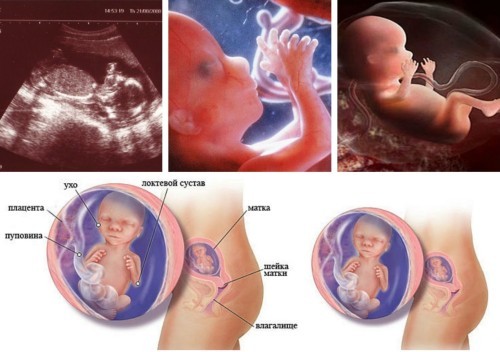

На 16 неделе малшыш весит приблизительно 80-100 г, а его рост колеблется в пределах 10-12 см. По размеру он похож на небольшое авокадо или средний помидорчик. Уже сформировалась система кроветворения и можно определить группу крови и резус. Малыш уже держит головку прямо и может вертеть ею из сторны в сторону. Начинают постепенно работать кишечник, желчный пузырь и печень. Также работают почки и мочевой пузырь, малыш начинает ходить "по-маленькому" и делает это довольно часто — примерно каждые 45 минут. Однако повода для беспокойства нет. Околоплодные воды меняются около 10 раз в сутки и абсолютно стерильны. Половые органы четко диференциированы и на узи будущим родителям уже уверенно скажут пол малыша.

На середине второго триместра- 16ой неделе плод развивается и становится более пропорциональным.

Его рост составляет 10-12 сантиметров

А вес 80-90 грамм.

По ощущениям четвертый месяц беременности не слишком тяжело переносится, токсикоза уже нет. Зато появляется бурный аппетит